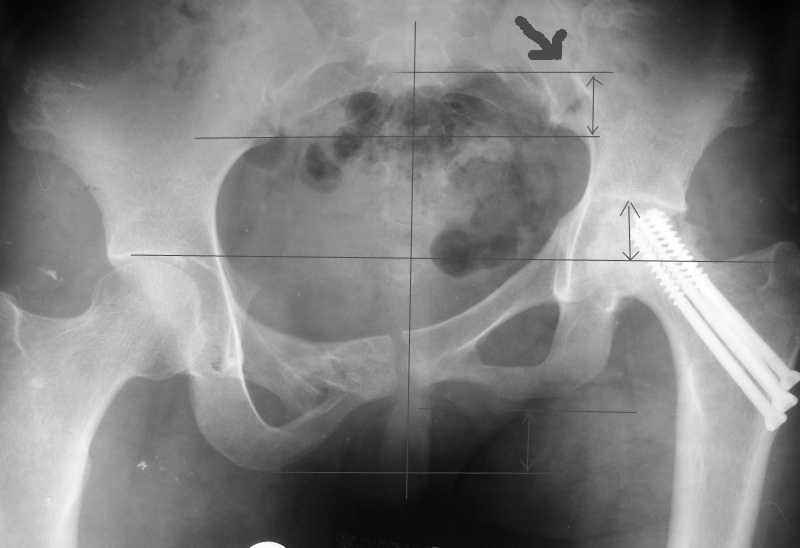

Согласен с Рунковым. Девочка молодая. Имеется ассиметричное расположение вертлужных впадин в прямой проекции. Так как повреждение таза было вертикально-нестабильное, вероятно имеется так же ассиметрия в передне-заднем направлении. Конечно протезом можно компенсировать имеющееся укорочение, но ассиметрично расположенные тазобедренные суставы приведут к нарушению двигательного стереотипа, нарушение походки, остеохондроз и т.д.

До сих пор идут большие дискуссии по поводу высокого центра ротации и единого мнения, насколько я знаю, нет. Компенсация длины, рычагов ягодичных мышц и т.д., а уж при вертикальном смещении таза,влияние его на последующее эндопротезирование просто не узнать (слишком мало наблюдений и много факторов, влияющих на конечный результат). Фото лишний раз подтверждают, укорочение за счет контрактуры.

Привет, Макс. Не торопись, посмотри внимательно на истинную картину. Толстая стрелка указывает на нижний край смещенного кп сочленения.

Поэтому считаю, что Принять какое-либо решение без кт и дополнительных проекций неразумно.

разговоров нет, смещение значимое, какое оно было, такое и осталось. Будут проблемы и с сидением и с осанкой и т.д. Идеальным вариантом было бы, конечно, исправить деформацию, а потом запротезировать. Но... цена вопроса. сейчас деформация, судя по костной мозоли, стабильная, и таз несет основную свою функцию - опорную, явно КПС не болит. Превратить стабильную деформацию в нестабильную и потом ее исправить - задача непростая, но выполнимая. Оперативное лечение будет сложное, скорее всего многоэтапное и длительное. С определенными рисками, общехирургическими и специфическими, например несращение зоны остеотомий - нестабильный таз, ризидуальное смещение (в пределах 1 см вполне вероятно). Если считать, что на тазе укорочение см 3, остальные 5. все-таки сгибательно-приводящая контрактура. На протезе от контрактуры можно избавиться, да и см 2 удлинить за счет опила, головки. В такой ситуации решение должна принять пациентка и оно должно быть действительно информированным.